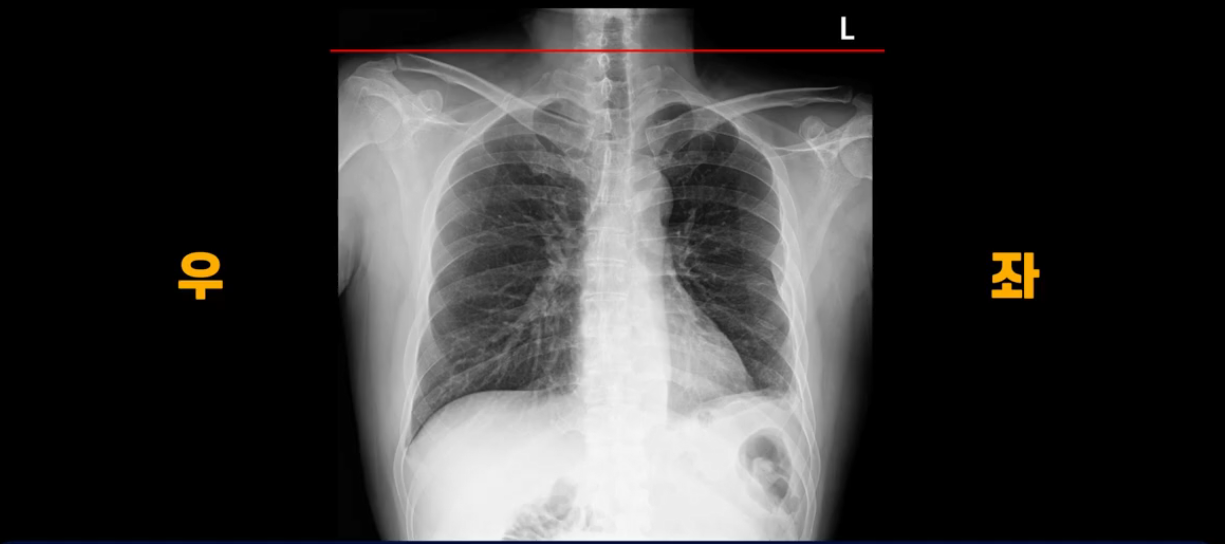

이분 X-ray 사진을 보시죠. 쇄골을 보면 어깨높이가 좌우가 완전히 달라져 있습니다.

몸이 완전히 틀어져 버린 겁니다. 이렇게 몸이 뒤틀리니까 보존 치료 10개월 후에는 한쪽 팔이 저리는 목디스크 증상까지 생기게 됩니다.